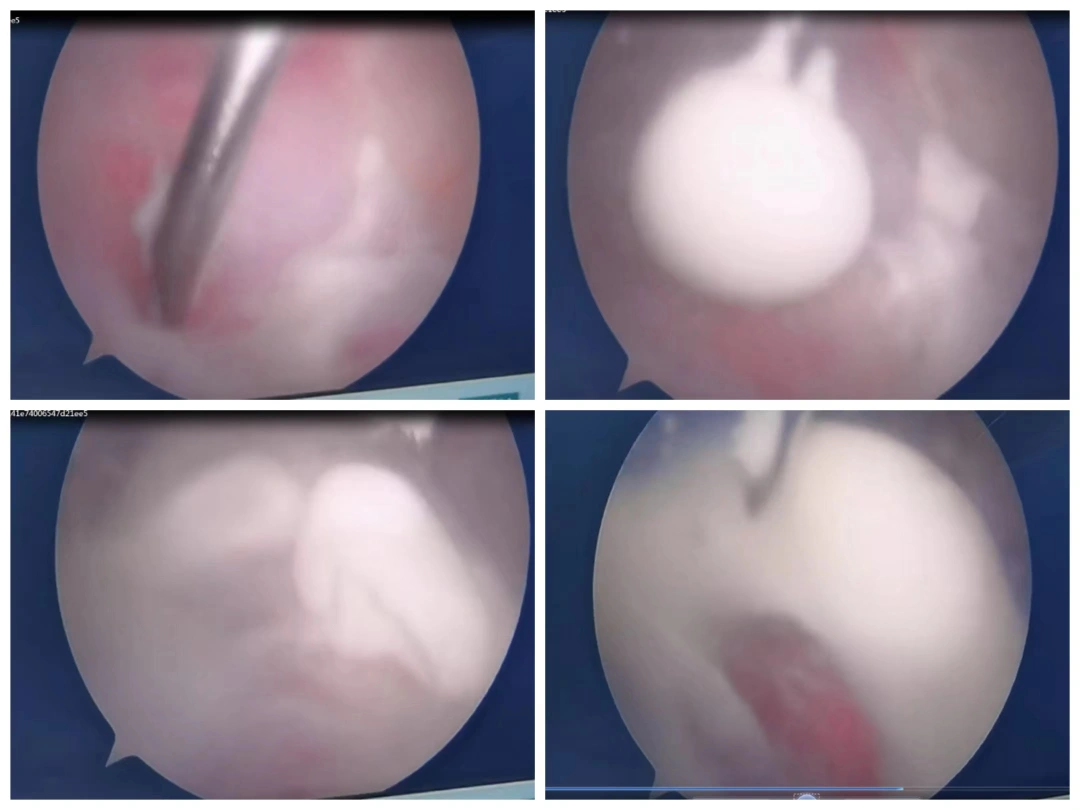

△术中,肌腱内喷出白色“牙膏”

值得注意的是,手术过程中出现了“神奇”的一幕。为刘阿姨主刀进行关节镜手术的李宝军主任医师介绍,当用探钩轻轻拨开肌腱钙化灶,肌腱内立即喷出了大量“牙膏”状白色物质,其实这是还没有完全钙化沉积的钙化灶释放出来的缘故,白色喷出物质就是钙化性肌腱炎的老巢。